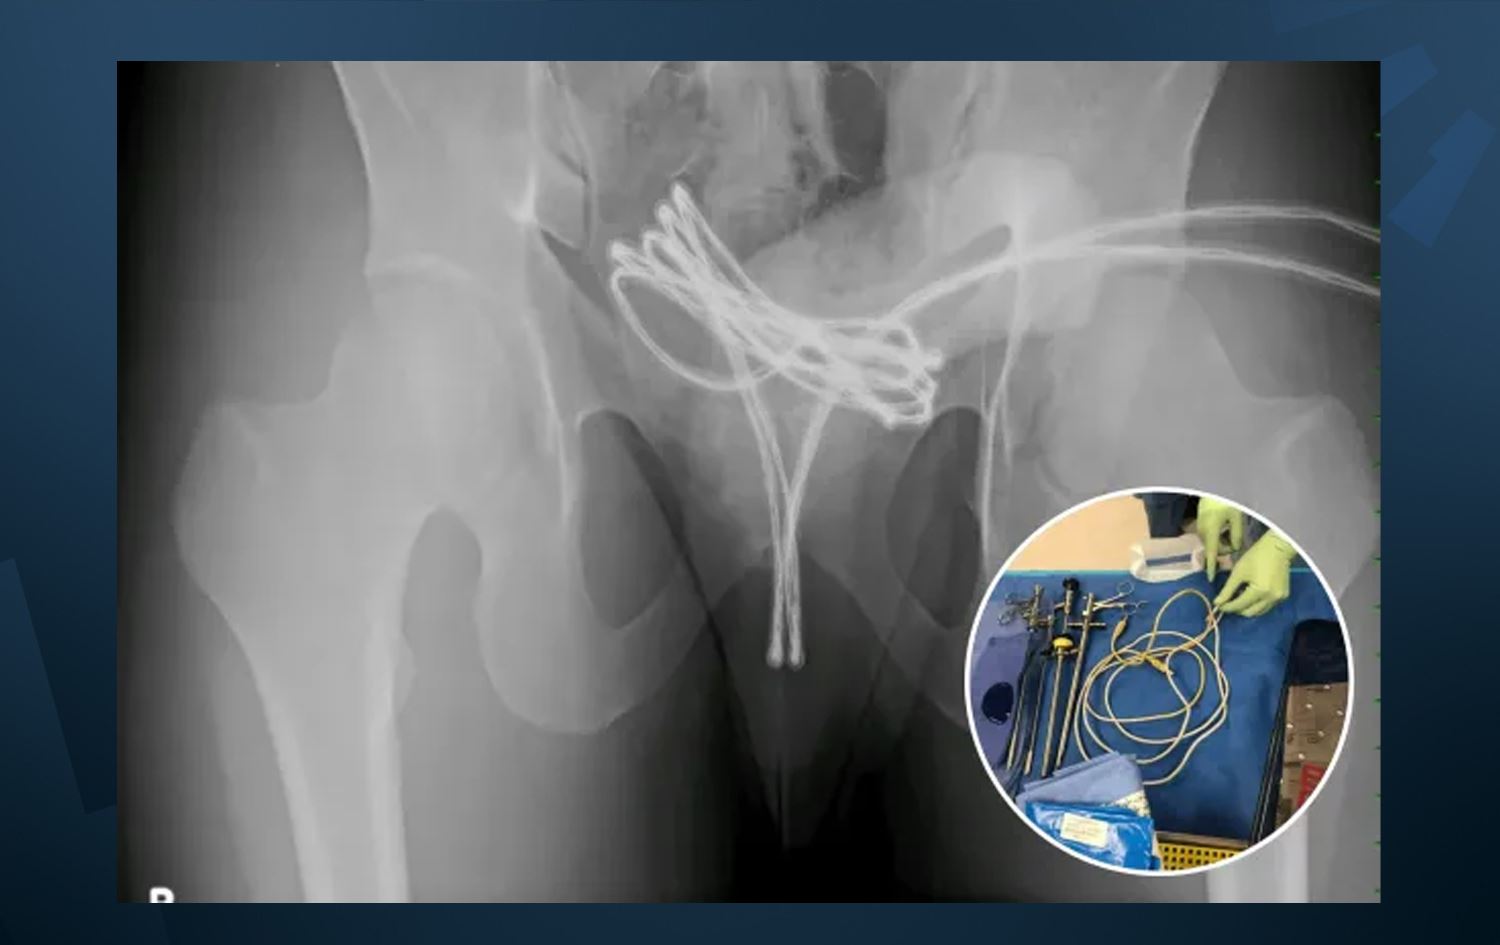

لە ئەمریکا کوڕێکی 21 ساڵان ''بۆ زیادبوونی ئارەزووی سێکسی'' کێبڵێکی USB دەخاتە نێو ئەندامی زاوزێی، پزیشکەکەی دەڵێت: کێبڵەکە تاوەکو میزڵدانی رۆیشتووە و برینداری کردووە.

گەنجەکە دانیشووی هەرێمی پێنسیلڤانیایە و بەپێی نەخۆشخانەی کۆلێژی پزیشکیی زانکۆی رێکسڵی ئەمریکا، ئەو 21 ساڵانە کە زانیویەتی ناتوانێت کێبڵەکە دەربهێنێتەوە، چووە بۆ نەخۆشخانە.

بەگوتەی گەنجەکە، ئەو کارەی بۆ ئەوە کردووە کە ئارەزووی سێکسیی زیاد بکات، پزیشکی سەرپەرشتیاری کەیسەکەش دەڵێت: کێبڵەکە دەرهێنانی قورس بوو، چونکە گەیشتبووە میزڵدان و تووشی برین و هەوکردنی تووندی کردبوو.

هۆشداری جیددیش دەدەن لەوەی، ئەو رێگەیە هەڵە و مەترسیدارە و هیچ پەیوەندیی بە ئارەزووی سێکسییەوە نییە، بەڵکو دەکرێت ببێتەهۆی 'تێکچوونی چووک، نەزۆکی، برینی میزەڕۆ، تێکچوونی میزڵدان و هەوکردنی تووند'.